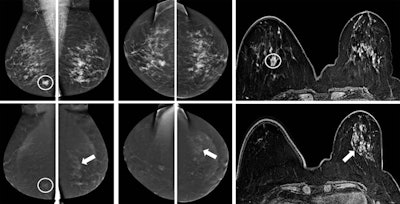

A 57-year-old woman was referred from a private clinic for an ill-defined irregular mass in the right breast, enhancing on both CESM and MRI (circles). CESM also showed diffuse enhancement throughout the left breast, for which random biopsies were taken, showing lobular carcinoma in situ (LCIS). Because of its extent, an MR-guided biopsy was recommended by the multidisciplinary team, again showing LCIS. Based on these findings and the patient's preference, a bilateral mastectomy with reconstruction was performed. Final pathology showed invasive carcinoma of no special type in the right breast, but 10 invasive lobular cancer foci varying from 3 mm to 10 mm in the left breast surrounded by LCIS. Images courtesy of Dr. Marc Lobbes."I think it is the combination between your mammographic image (in which you can appreciate the morphology of lesions very well through the high spatial resolution) and the enhancement seen on the recombined images," he told ECR Today. "On MRI, especially with small foci, you see them enhancing, but because of the spatial resolution, it is much more difficult to appreciate the subtle morphology."